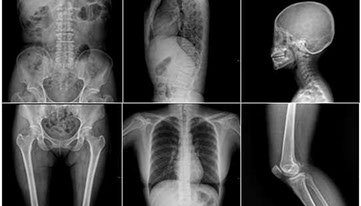

Les chiropraticiens utilisent cet outil pour diagnostiquer et analyser :

• l'alignement de la colonne vertébrale , des courbes cervicales, thoraciques et lombaires

• l'intégrité ou l'usure des disques intervertébraux

• l'usure du cartilage articulaire ( hanches, genoux, etc)

• la minéralisation osseuse

• les tissus mous ( bursite, abdomen, poumons, gorge, etc)